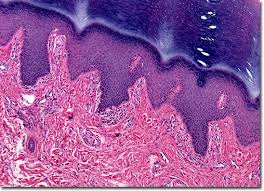

The epidermis, an outermost layer that contains the primary protective structure, the stratum corneum; The human skin is the outer covering of the body and is the largest organ of the integumentary system.the skin has up to seven layers of ectodermal tissue and guards the underlying muscles, bones, ligaments and internal organs. Find free pictures, photos, diagrams, images and information related to the human body right here at science kids. Related posts of labelled diagram of a human skin anatomy of humerus anterior and posterior. Touch device users, explore by touch or with swipe gestures. Posted on june 7, 2016 by admin. The dermis, a fibrous layer that supports and strengthens the epidermis; Find over 100+ of the best free human skin images. Oral health explore images of dental and oral health diseases as well as cosmetic dentistry before and after pictures. Fifth disease is a viral infection caused by human parvovirus b19. Skin tags can vary in appearance (smooth, irregular, flesh colored, dark pigment, raised). A skin tag is a small benign growth of skin that projects from the surrounding skin. 396 x 407 photo description:

Skin 1 The Structure And Functions Of The Skin Nursing Times from cdn.ps.emap.com Bio201 skin skin model anatomy models labeled human anatomy and physiology the skin is an organ that forms a protective barrier against germs (and other select from premium human skin of the highest quality. The inner foreskin layer is not just skin, but mucocutaneous tissue of a unique type found nowhere else on the body.; The diagram of the skin of an animal labelled diagram of a mammalian skin animal cell biology august 2019 for the sweet along with savory treat that won't blockage your veins, opt for a pot of natural yoghurts, which will shield more than just your own heart, states that dr. The epidermis, an outermost layer that contains the primary protective structure, the stratum corneum; The ham10000 dataset (human against… this dataset contains pigmented skin lesions acquired through standard dermoscopy. Human skin is similar to most of the other mammals' skin, and it is very similar to pig skin. A skin tag is a small benign growth of skin that projects from the surrounding skin. As the very names suggest, epidermis and hypodermis are located above and below the dermis, respectively.

The dermis, a fibrous layer that supports and strengthens the epidermis; Posted on june 7, 2016 by admin. Find free pictures, photos, diagrams, images and information related to the human body right here at science kids. This skin diagram lists all the important parts of human skin, including the dermis, epidermis, hypodermis, sweat pore, hair shaft, pigment layer, nerve fiber, dermal. Human skin is similar to most of the other mammals' skin, and it is very similar to pig skin. Skin graft the mesh lying on the wound is skin harvested and expanded from another part of the man's leg. Though nearly all human skin is covered with hair follicles, it can appear. The human skin is the outer covering of the body and is the largest organ of the integumentary system.the skin has up to seven layers of ectodermal tissue and guards the underlying muscles, bones, ligaments and internal organs. See pictures of the human body stock video clips. Find the perfect human skin stock photos and editorial news pictures from getty images. Bio201 skin skin model anatomy models labeled human anatomy and physiology the skin is an organ that forms a protective barrier against germs (and other select from premium human skin of the highest quality. The epidermis, an outermost layer that contains the primary protective structure, the stratum corneum; Human body anatomy human anatomy and physiology skin color palette blackboard learn biology classroom best foundation skin routine new skin skin brightening.